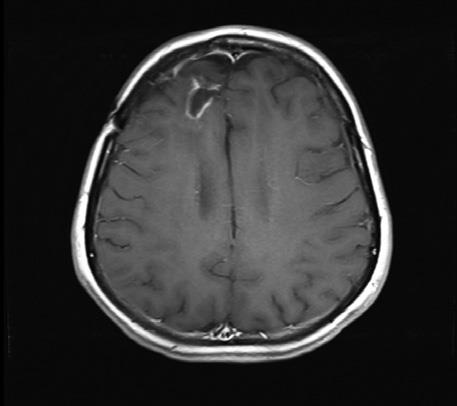

Сейчас проходят и вовсе поразительные клинические испытания. Ученые из Университета Дьюка используют другую иммунную стратегию, модифицируя вирус полиомиелита. Идее борьбы с раком с помощью вирусов больше ста лет, но необходимые для экспериментов технологии и технические новинки появились сравнительно недавно. Последний случай заражения полиомиелитом случился в США в 1979 году. Ученые Университета Дьюка заметили одно интересное свойство вируса: он убивает клетки, попадая в них через «дверь»-рецептор. Как оказалось, рецептор для вируса полиомиелита присутствует на большинстве клеток твердых опухолей – раков легких, груди, мозга, простаты, – а вот на большинстве нормальных клеток отсутствует. Проблема лишь в том, что вирус может прикрепляться еще и к клеткам нервной системы – нейронам. Когда вирус убивает их, это приводит к мышечному параличу. Если удалить болезнетворную часть вируса, заражающую нормальные нейроны, и подменить ее безвредным вирусом простуды, а ту часть, что прикрепляется к раковым клеткам и уничтожает их, оставить, то мы получим безопасный вирус. Вирус впрыскивается прямо в опухоль, заражает несколько раковых клеток и убивает их, в то же время активизируя иммунную систему. Она просыпается: «Эй, это же полиомиелит!» – и вместе с вирусом убивает еще и «ни в чем не повинные» клетки опухоли. Вирус, по сути, помечает опухоль как «чужеродный предмет» и заставляет иммунную систему тела идти в бой. Исследования с вирусом полиомиелита на данный момент ведутся в основном на пациентах с продвинутой стадией глиобластомы – одного из самых смертоносных и агрессивных видов рака мозга, который часто убивает через несколько недель после того, как все стандартные способы лечения перестают работать. Ученым удалось продлить жизнь нескольких пациентов на месяцы и даже годы [9]. ![]() ![]() ![]() Энцефалограммы 20-летнего студента, которого лечат модифицированным вирусом полиомиелита (PVS-RIPO), вводимым через катетер, подсоединенный прямо к опухоли. Слева – опухоль до лечения (затененная область в верхней левой части мозга). В середине – опухоль после двух месяцев лечения (она кажется даже больше из-за воспаления, вызванного иммунным ответом). Справа – опухоль, уменьшившаяся после девяти месяцев лечения. Идея использования собственной иммунной системы для лечения рака, конечно, романтична, но и в ней есть свои опасности. Наша иммунная система, если ей позволить работать на полную мощность, очень сильна. Спускать ее с тормозов, даже в надежде, что она может убить дьявольские, сошедшие с ума клетки, очень рискованно. Некоторые пациенты, попробовавшие иммунотерапию, умерли от тяжелейших осложнений, вызванных неудержимой иммунной системой, которая вместе с раком начала атаковать здоровые, жизненно необходимые ткани и органы. С помощью клинических испытаний ученые надеются преодолеть эту трудность. Иммунотерапия – важное оружие против рака и останется таковым и в дальнейшем, но сейчас она подходит лишь для определенных видов рака и только некоторых пациентов. Главная трудность – заранее определить, кому она подойдет. Кроме того, нужно лучше понять, какое сочетание «checkpoint ингибиторов» или других препаратов лучше всего помогает иммунной системе бороться с раком. На самом деле, чем больше мутирует рак, тем легче с ним бороться с помощью иммунотерапии, потому что его клетки становятся все более «инородными на вид» для организма. Иными словами, чем ненормальнее становится опухоль, тем труднее ей избегать обнаружения со стороны иммунной системы, особенно после того, как лекарственная терапия уже приводит ее в состояние постоянной готовности и оснащает специальными «очками ночного видения». Это явление было недавно описано в выдающейся статье в New England Journal of Medicine командой исследователей из Онкоцентра имени Сидни Киммела в Университете Джонса Хопкинса [10]. ДНК в теле постоянно ремонтируется с помощью инструментов для «репарации ошибочно спаренных нуклеотидов». Эта группа исследователей обратила внимание на гены репарации ошибочно спаренных нуклеотидов, которые кодируют систему, используемую телом для распознавания и ремонта испорченной ДНК, они либо присутствуют, либо нет. Выяснили, что вне зависимости от типа рака опухоли, у которых эта система не работает, с большей вероятностью реагируют на лекарство, блокирующее PD-1 и снимающее с тормозов иммунную систему, чем те, у которых репарация работает нормально. Иными словами, чем хуже клетки опухоли умеют ремонтировать ДНК, тем лучше пациенту помогает лечение. Иммунотерапия, скорее всего, не сможет лечить рак в одиночку: ее будут использовать в сочетании с другими методами, в том числе химиотерапией, радиационной терапией и молекулярно-таргетированными лекарствами. Тем не менее она станет незаменимым инструментом, который будет даже еще сильнее благодаря дополнительному «оружию». Некоторые пациенты, проходившие иммунотерапию, умерли от осложнений, вызванных неудержимой иммунной системой, которая вместе с раком начала атаковать здоровые, жизненно необходимые ткани и органы. Одно из удивительных открытий, связанных с иммунотерапией, состоит в том, что многие люди, которые ее попробовали, говорили, что чувствуют себя лучше, несмотря на то что рак никуда не делся и даже в некоторых случаях рос. Но это проблема моей специальности. Единственный измеримый параметр успеха – уменьшение опухоли. Замедление ее роста, улучшение самочувствия или продление жизни дальше ожидаемого срока в онкологии обычно не считается «успехом». Если вы придете ко мне с 5-сантиметровой раковой опухолью, я пропишу вам лечение, и через несколько месяцев ваша опухоль увеличится до 7 сантиметров, подействовало ли лечение? Может быть, без лечения опухоль была бы уже размером 15 сантиметров? По большей части, пробуя новые лекарства, замедляющие или останавливающие рак, и врачи, и пациенты двигаются на ощупь. В любом рандомизированном клиническом испытании лекарство, возможно, поможет группе пациентов в целом прожить дольше, но очень трудно определить, что оно делает в каждом конкретном случае. Если вы, например, сможете спокойно прожить два года, принимая лекарство X, не все ли вам равно, насколько у вас большая опухоль, если побочные эффекты вполне терпимы, а чувствуете вы себя хорошо? Ни один пациент мне еще не говорил чего-либо вроде «Лучше бы я умер в прошлом году». Даже самые больные пациенты не жалеют, что прожили дольше, чем ожидалось. Они готовы практически на все, чтобы прожить один лишний день, и часто готовы на любые, даже самые абсурдные с виду эксперименты. Проще говоря, они готовы идти на риск вместе со мной в нашей общей доблестной битве. |